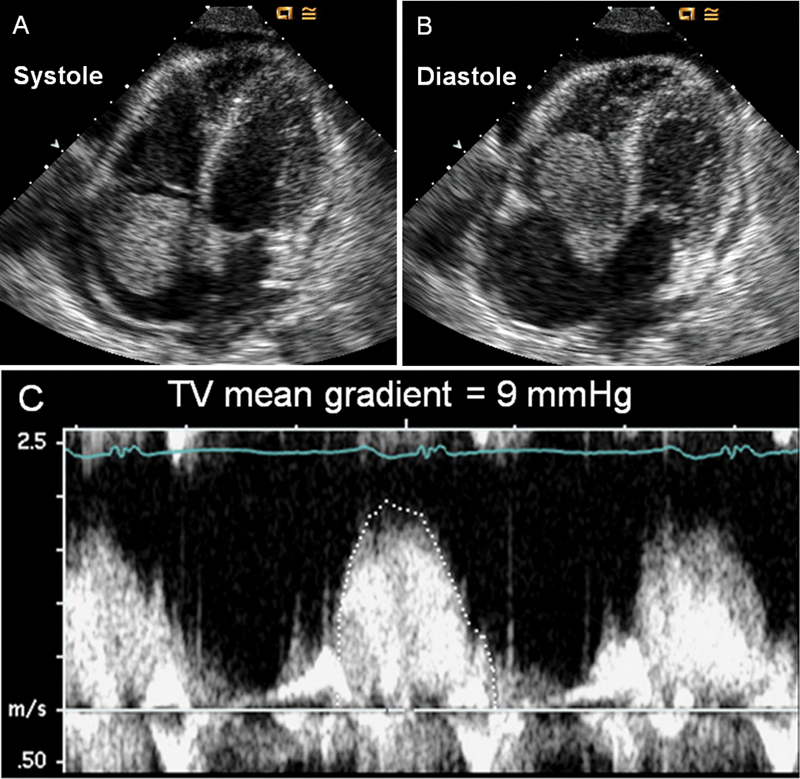

فحوصات تشخيصية لبعض امراض القلب والشرايين التاجية